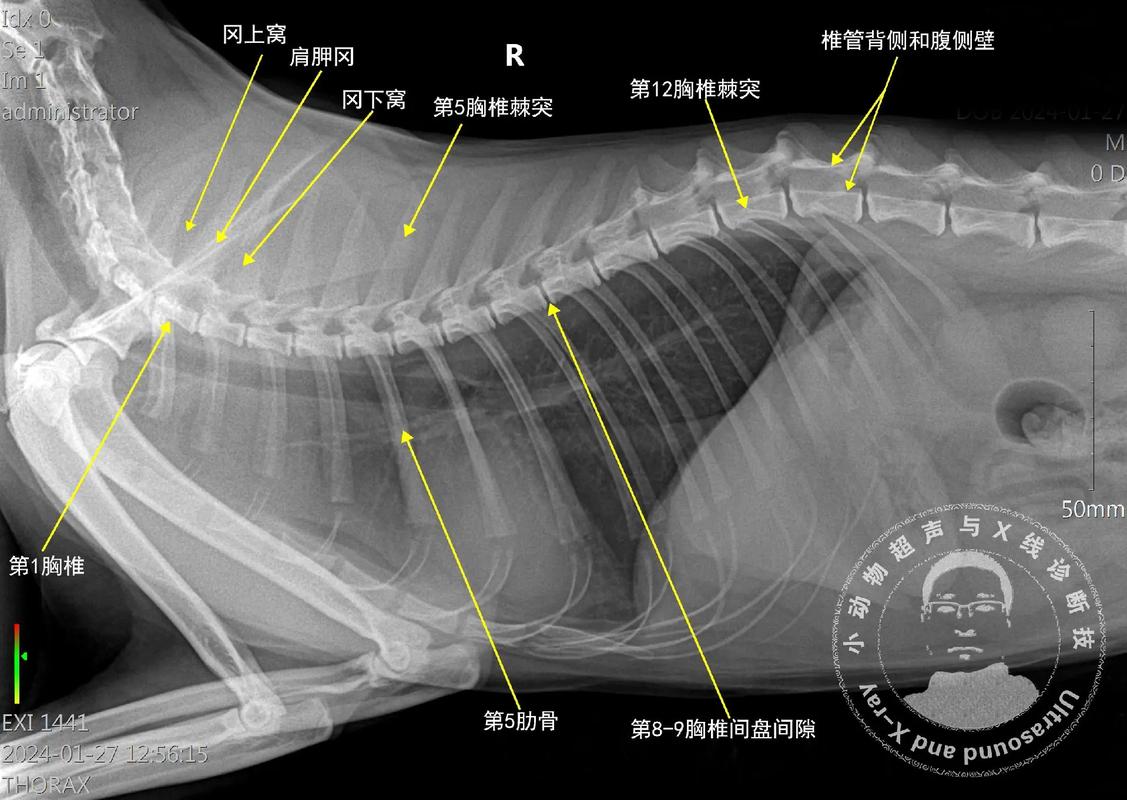

猫咪的胸骨突出是一种常见的病症,也称为胸骨异常突出或凸胸。这种情况可能是由于遗传因素、营养不良或发育异常导致的。猫咪的胸骨突出可以导致呼吸困难、体力下降以及胸部变形等问题。首先,建议您立即带上猫咪去兽医那里进行专业的检查和确诊。兽医会观察猫咪的胸部骨骼结构,并进行X光检查来确认诊断。治疗猫咪胸骨突出的方法因情况而异。

猫胸骨剑突外翻可能是由先天发育或其他外力造成的。在这种情况下,建议尽快带猫咪去宠物医院进行检查和治疗,不要拖延。恢复可能需要一两个月的时间,但具体时间会根据猫咪的个体情况和治疗方案而有所不同。如果猫咪的胸骨剑突外翻过于明显,可能需要进行手术治疗。